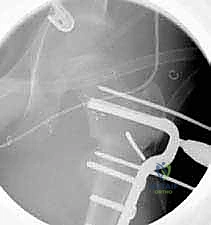

3. إدخال السلك الدليلي (Guide Wire)

تحت توجيه الأشعة السينية المباشرة داخل غرفة العمليات (C-arm)، يقوم الدكتور هطيف بإدخال سلك دليلي في عنق ورأس عظم الفخذ بالزاوية الصحيحة والمحسوبة بدقة.

6. التثبيت الداخلي القوي (Internal Fixation)

لضمان التحام العظم في وضعه الجديد، يستخدم الدكتور هطيف نظام تثبيت عالمي يتمثل في صفيحة الشفرة الزاوية (AO 90-degree Blade Plate) أو مسامير وصفيحة مخصصة للأطفال. يتم إدخال الشفرة في عنق الفخذ، وتثبيت الصفيحة على جسم العظم باستخدام براغي معدنية قوية.